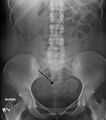

A very large (9 cm) fibroid of the uterus which is causingpelvic congestion syndrome as seen on CT |

Two calcified fibroids (in the uterus) |